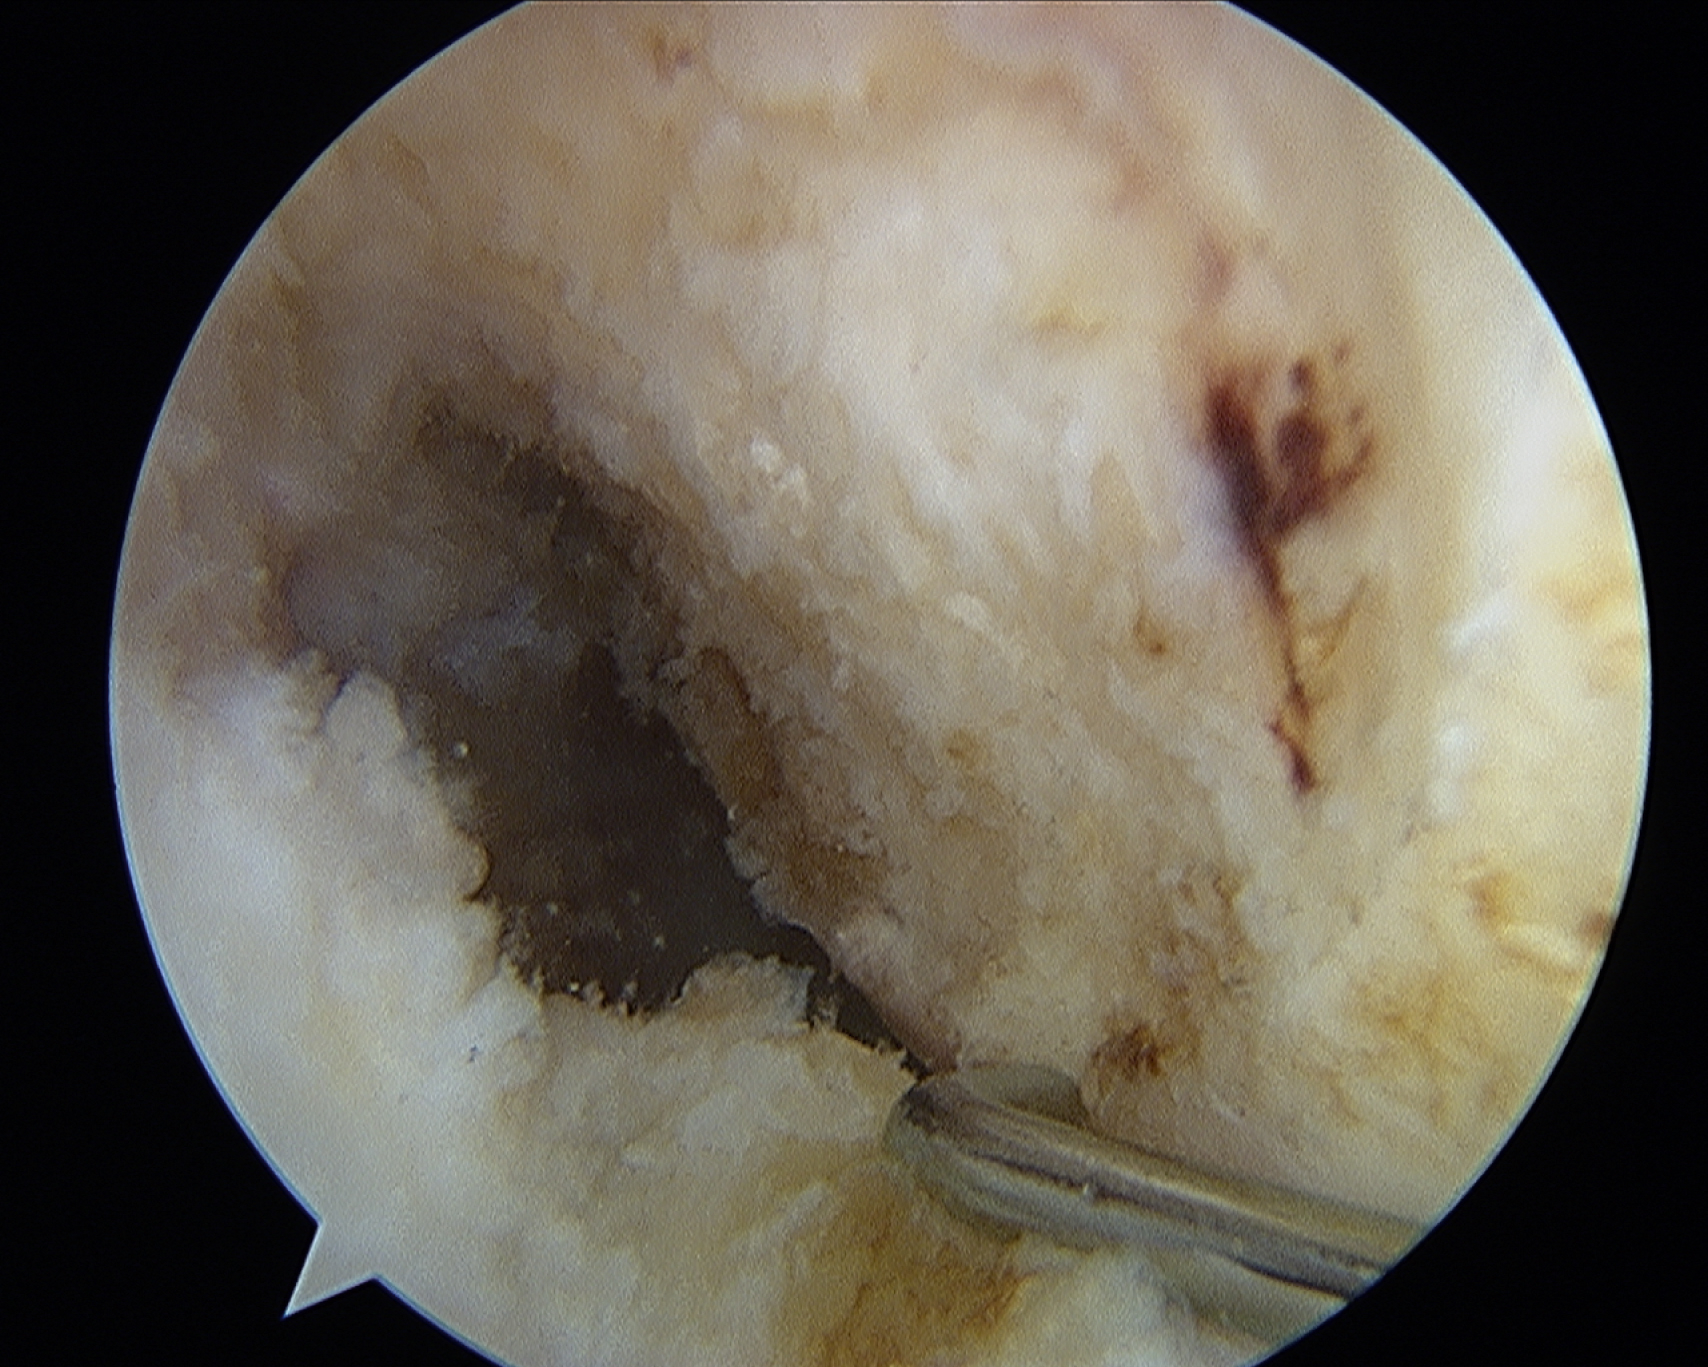

Viewing the notch from the lateral portal to assess the ACL insertional anatomy is a challenge. The lateral portal view allows a good evaluation of height within the notch but little perspective on depth within the notch. The medial portal provides an excellent view of the anatomy (

), but the medial portal is a working portal and generally only used for viewing when verifying an anatomic location. Thus the site for a femoral tunnel placement is identified when viewing from a lateral portal, which has limited perspective. Multiple strategies have evolved to address this challenge.

This view from the medial portal demonstrates perspective on height and depth within the notch. The lateral intercondylar ridge and remnants of the anterior cruciate ligament are often hard to identify as landmarks for femoral tunnel placement.